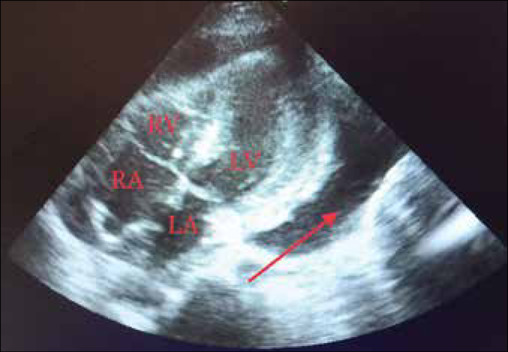

Complications involving the heart are rare in leptospirosis, and cardiac tamponade is still rarer. We report the case of a 42-year-old hypertensive woman who presented with complaints of cough for 2 months and breathlessness for 1 month. One month later, she developed shortness of breath and loss of consciousness. The patient had a history of hemiparesis. Serum anti-Leptospira immunoglobulin M ELISA was positive. Ultrasound showed pericardial tamponade and hemorrhagic collection. Two-dimensional echocardiography showed minimal effusion posterior to the left ventricle and no effusion present to the right ventricle. High-resolution computerized tomography revealed patchy areas of ground glass opacities in bilateral upper and bilateral lower lobes, prominent bronchovascular markings bilaterally, and minimal pericardial thickening. Magnetic resonance imaging of the brain showed small chronic infarcts in bilateral corona radiata and basal ganglia. A magnetic resonance angiogram of the brain showed a basilar top aneurysm, which was an incidental finding. No signs of rupture of the aneurysm were seen. Digital subtraction angiography showed 50%-70% stenosis at the junction of the V3-V4 segments of the vertebral artery. The right lower limb immobilization, along with ecosprin, ivabradine, amlodipine, and fluconazole, was started, to which the patient responded well.